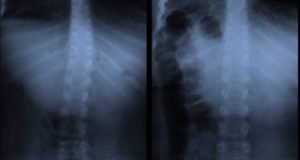

Deformiteti kičme kod dece – šta je skolioza i kifoza, njihova...

Razdoblje intenzivnog rasta i razvoja je najkritičnije kada su u pitanju kičmeni deformiteti kod dece. Kriva kičma kod dece je direktna posledica svakodnevnih životnih...